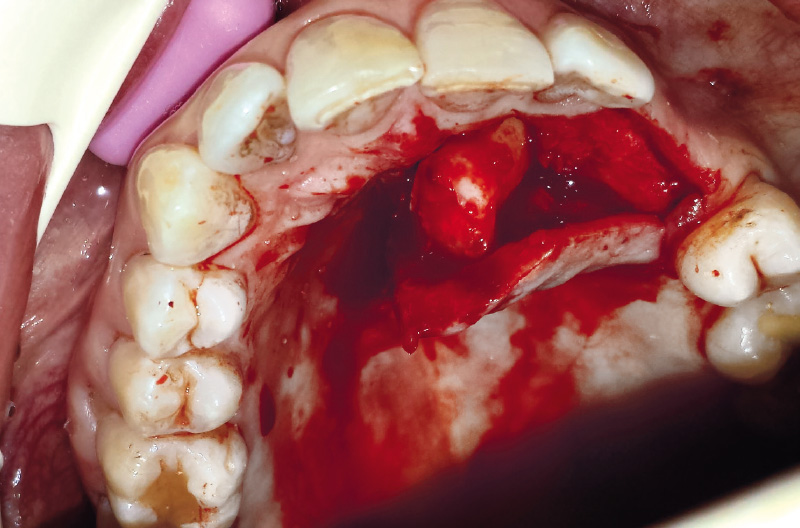

Una volta sollevato il lembo ed apprezzato la bozza ossea contenente la corona del 23, si pratica una breccia ossea per esporre la cuspide del canino e si effettua l’odontotomia coronale al fine di rendere più agevole le manovre estrattive della porzione cervico-radicolare (Figg. 6, 7).

Una volta estratto l’elemento 23 (Fig. 8) si inseriscono due impianti, un impianto Leone 3,3x14mm in regione 23 e un impianto Leone 3,3x12mm in regione 24, entrambi circa 1 mm sotto cresta (Figg. 9, 10).